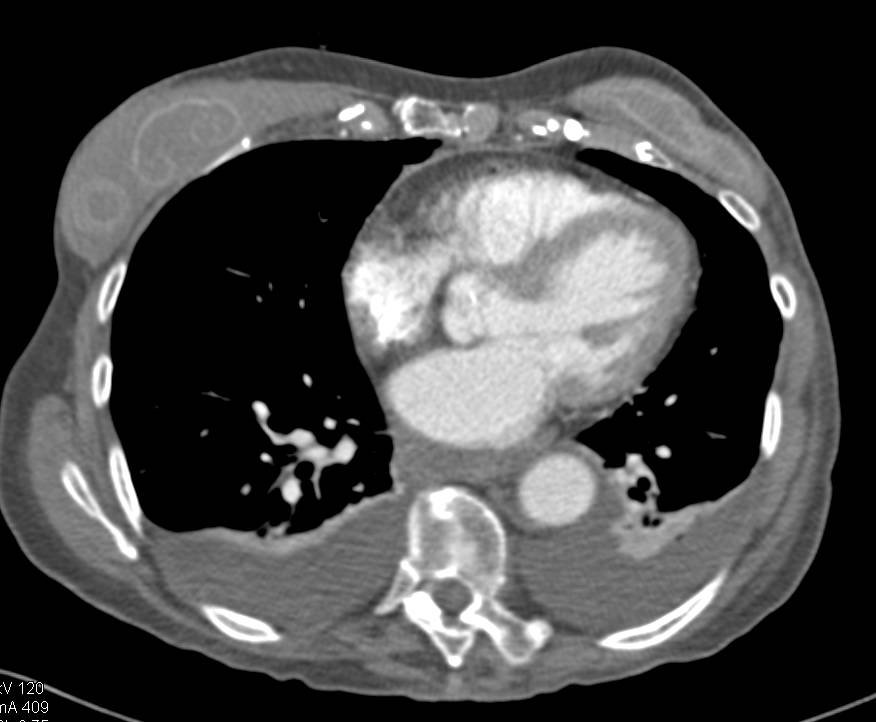

Esophageal Duplication Cyst